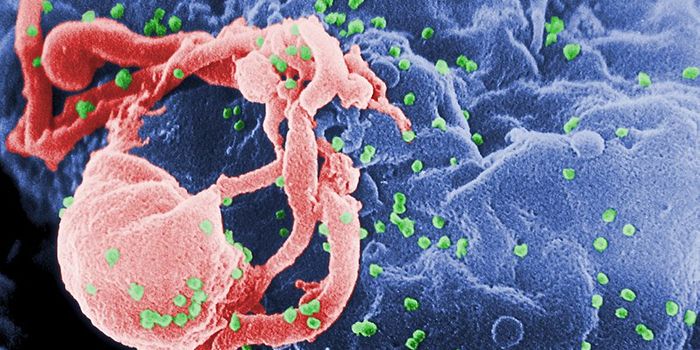

OCT 19, 2017Health & MedicineFor the first time, researchers dare to suggest they may have found a functional cure for HIV, the viral infection that ...